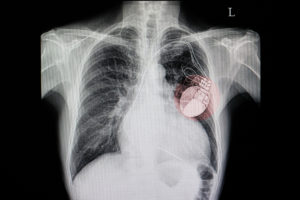

It might sound like nanotechnology hacking will happen far into the future, but some experts believe some experimental nanotechnology medical treatments will be in use in just two years. Additionally, medical technology already in use today has already been proven hackable. Johnson & Johnson advised users of one of its insulin pumps to not use the remote control feature of the device and to make sure to set a maximum insulin dose in case of hacking. Recently, the FDA recalled 500,000 pacemakers due to the risk of hacking. In 2015, researchers were able to hack into and deactivate a pacemaker set up on a mannequin, proving these are much more than fears: they are an inevitable reality.